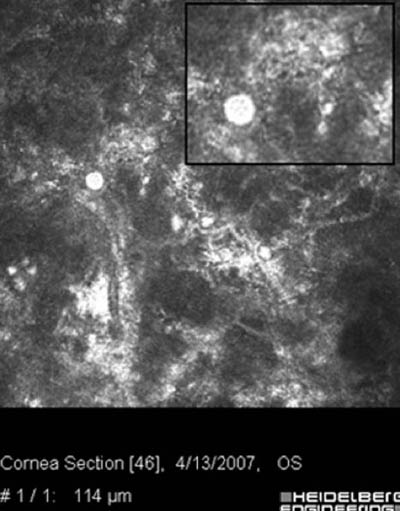

- Microscopia Confocal : 94 a 100% de especificidad y 80 a 84% de sensibilidad

Microscopía Confocal